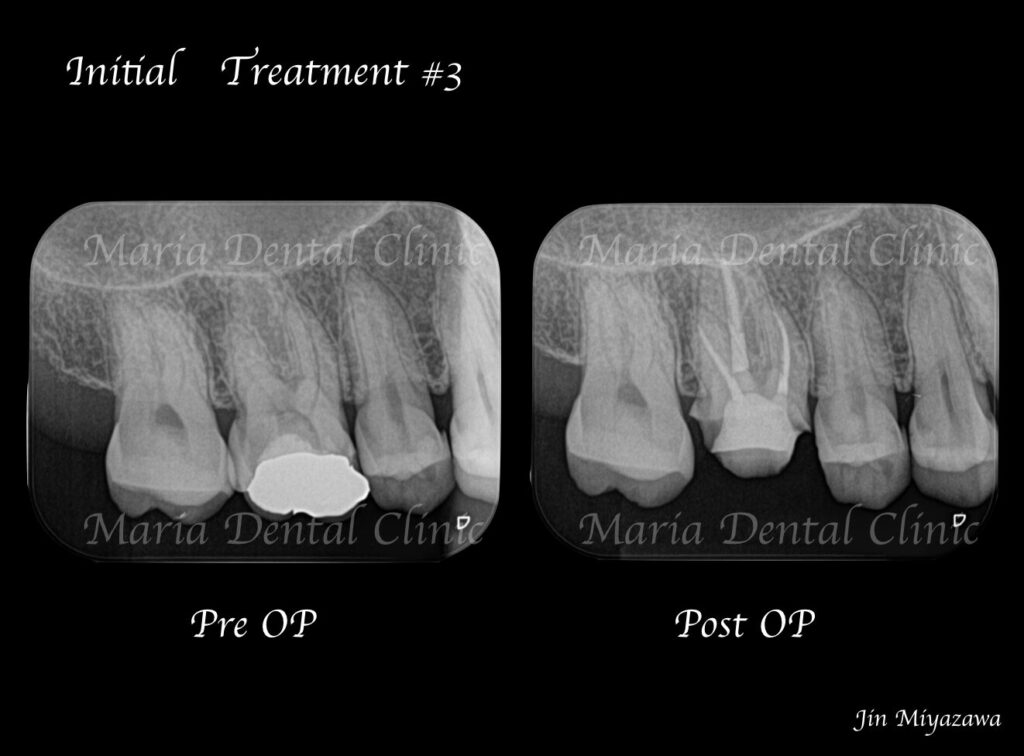

歯科用拡大鏡、歯科用顕微鏡下にて、軟化象牙質(虫歯)を除去後、歯髄を確認すると一部の歯髄には血流がなく部分壊死を起こしていることがわかる。

今回は術前に歯髄炎による疼痛を確認していたため、水酸化カルシウムを貼薬した後、2回目の治療にて根管充填、支台築造処置を終了させている。

|歯の寿命を左右する初回根管治療_術前術後のレントゲン画像比較-1024x756.jpg)